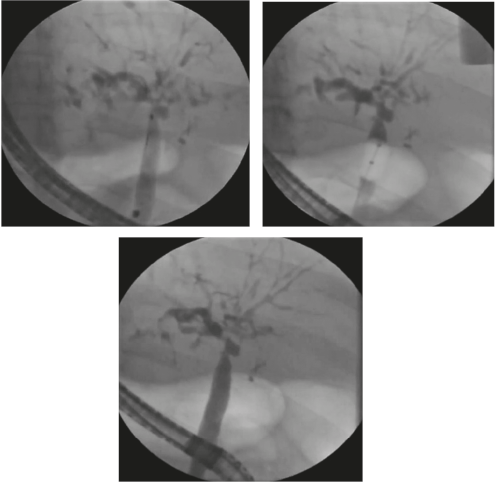

Las guías primarias para la CEP recomiendan la dilatación con balón como tratamiento endoscópico de primera línea (Figura 1). Si se decide realizar cualquier intervención biliar endoscópica se debe estar alerta ante el riesgo de colangitis bacteriana y administrar siempre antibióticos profilácticos de acuerdo con los perfiles de resistencia locales (39). Siempre se debe evaluar la presencia de várices, ya que en los pacientes con la CEP el desarrollo de estas puede darse antes de que sea evidente la cirrosis (7).

Figura 1 Secuencia de colangiografía con estenosis en la confluencia, angiograma con balón y cepillado.

Debido a la naturaleza invasiva del procedimiento, entre el 7,3 y el 20 % tienen riesgo de tener complicaciones posendoscópicas, como la pancreatitis, colangitis, perforación de la vía biliar y hemorragia (40).